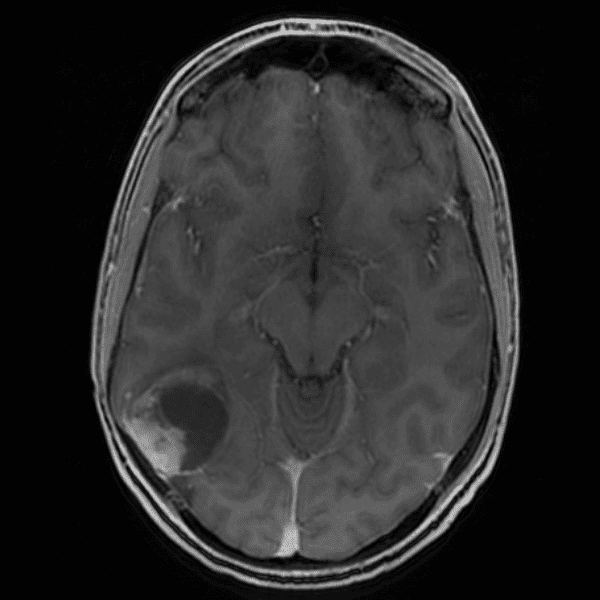

Classic Cases